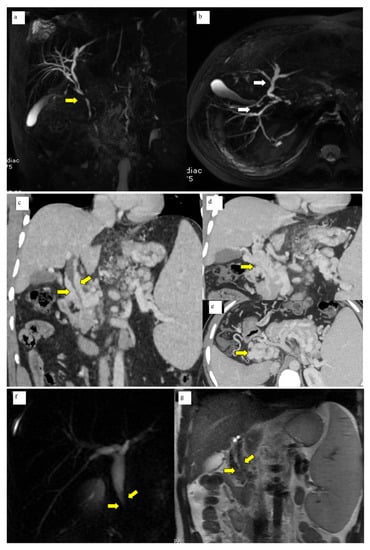

A total of 50 patients with portal cavernoma cholangiopathy were included in the study. The mean age of the patients was 26.2 ± 11.6 years. There was a male preponderance with male to female ratio of 2.6:1. Basic parameters are summarized in Table 1. Imaging characteristics were as follows: bilobar intrahepatic biliary radical dilatation in 98% and common bile duct abnormality in 100% of patients (Figure 1a, b). Extrinsic bile duct impressions were present in 77% (Figure 1c–e), stricture in 16% (Figure 1f, g), and smooth contour in 6% was observed. All strictures were <10 mm in length. Radiological findings are summarized in Table 2. Shunt surgeries were done in 52 patients, 6 underwent splenectomy and 2 cholecystectomies. Liver function tests were mild to moderately deranged with median levels of total bilirubin 1.5 mg/dL (IQR 0.8–2.4), SAP 109.5 IU/L (IQR 70–193), and GGT 25.5 IU/L (IQR 14.7–74).

(a) MRCP Coronal & (b) 3D axial MRCP showing extrahepatic (Bold yellow arrow) and intrahepatic biliary dilatation (bold white arrows) with ductal wall irregularity in a case of well-delineated portal biliopathy of a 16-year-old young boy. (c) Coronal Contrast-enhanced CT scan of the abdomen showing opacified paracholedochal collaterals (bold yellow arrows) along the length of the common bile duct causing extrinsic luminal compression. (d) Coronal Contrast-enhanced CT Scan of the abdomen showing multiple opacified portal cavernoma collaterals along the entire length of the common duct (bold yellow arrow), extending up to suprapancreatic segment. (e) Axial contrast-enhanced CT section of the upper abdomen shows portal cavernoma as a bunch of collaterals in the spleno-portal confluence and the SMV which cannot be separately identified from the collaterals (yellow bold arrow). (f) Coronal 2D Magnetic resonance cholangiopancreatography (MRCP) image showing narrowing of the distal common duct segment (bold yellow arrows) due to extra luminal collaterals seen as T2 hypointense flow voids (bold yellow arrows). (g) Coronal T2 WI of the MRI of the upper abdomen.